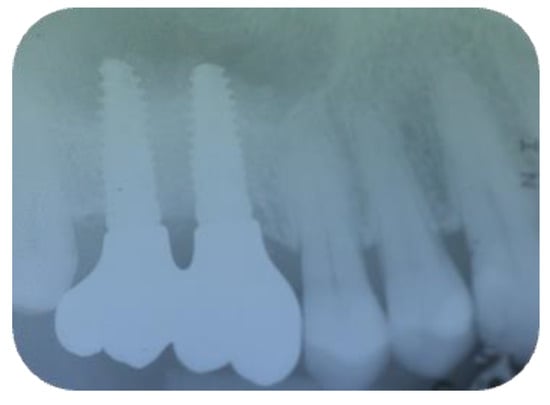

Long-Term Outcomes of Implants Placed in Maxillary Sinus Floor Augmentation with Porous Fluorohydroxyapatite (Algipore® FRIOS®) in Comparison with Anorganic Bovine Bone (Bio-Oss®) and Platelet Rich Plasma (PRP): A Retrospective Study

2. Materials and Methods

2.2. Follow-Up

3. Results